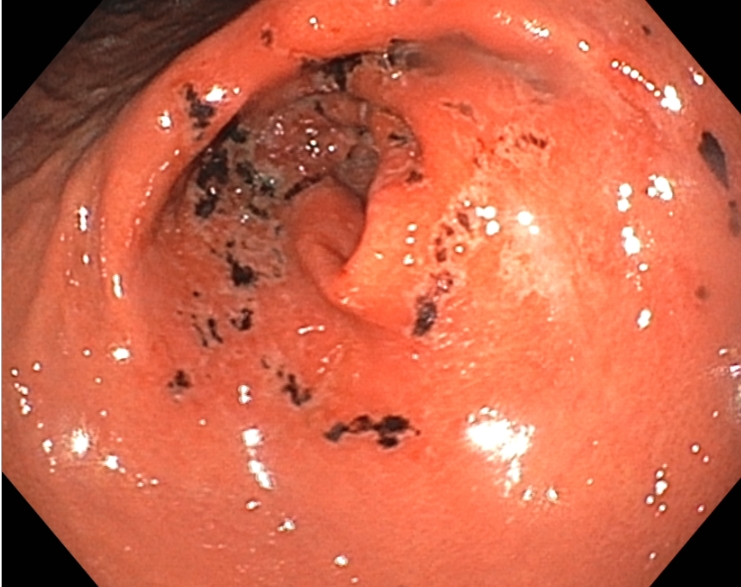

다음은 위내시경에서 확인된 위분문부와 유문부 점막에 생긴 급성위점막병변 사진입니다.